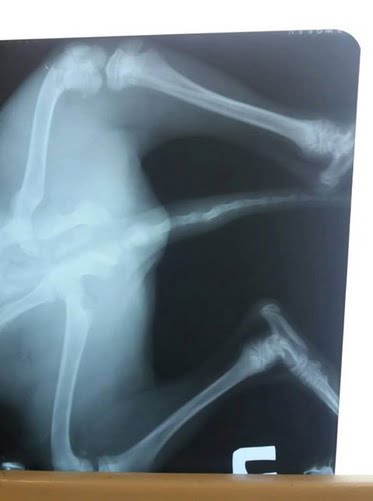

В один день (в субботу, 06.10.2018) в Корабельном районе на проезжей дороге были сбиты 2 собаки: 3-месячный щенок и старая собака.

фото щенка, сделанное Анной буквально за минуты до аварии и после

«В обоих случаях ни один водитель не остановился, чтобы помочь животным, которые остались лежать на дороге!!! Только благодаря зоозащитникам и нескольким небезразличным жителям района у собак есть шанс на ЖИЗНЬ! У них переломы, ЧМТ, лечение только за свой счет и благотворительные перечисления», — рассказала женщина.